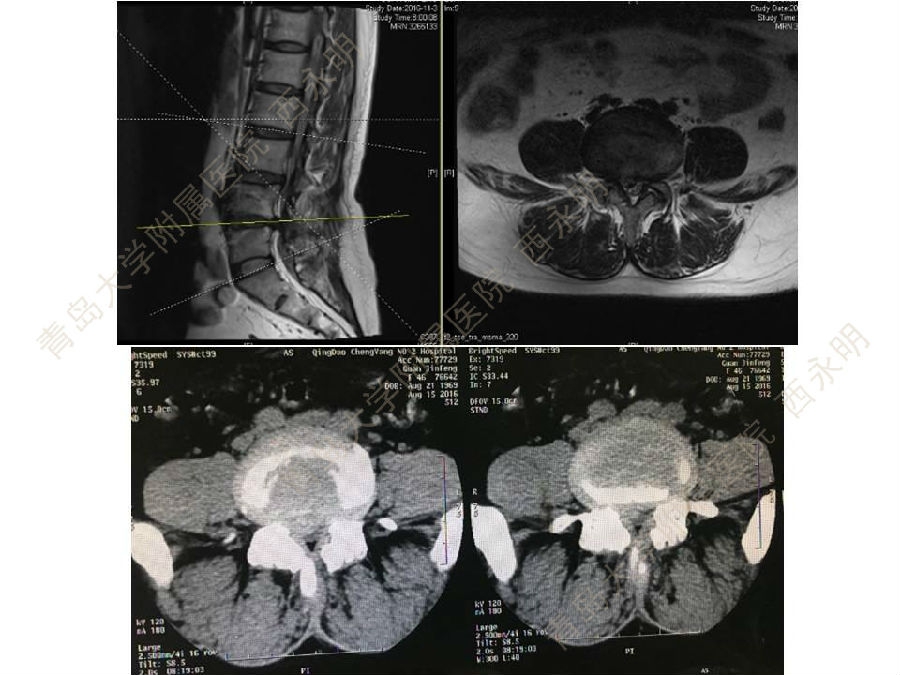

皮质骨螺钉技术及临床应用

颈椎伤病、脊柱畸形和脊柱肿瘤以及颈胸腰椎退变性疾病的微创治疗。长期从事临床一线的医、教、研工作,在多年的临床实践中积累了丰富的经验,并形成了以脊柱外科为专业方向,以颈椎外科、脊柱畸形和脊柱肿瘤为专业特色。